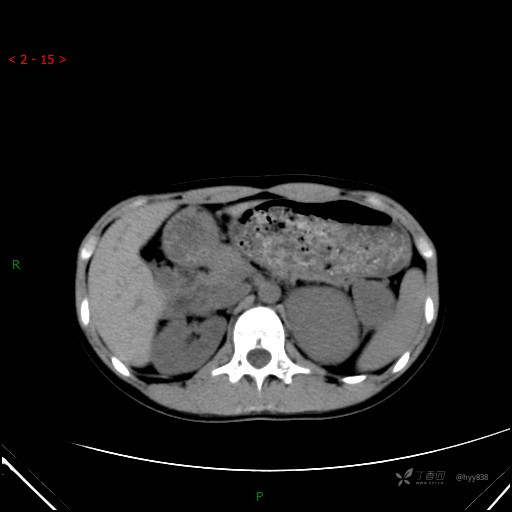

CT值